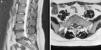

Síndrome de cola de caballo tras tratamiento quiropráctico

Cauda equina syndrome after chiropractic treatment